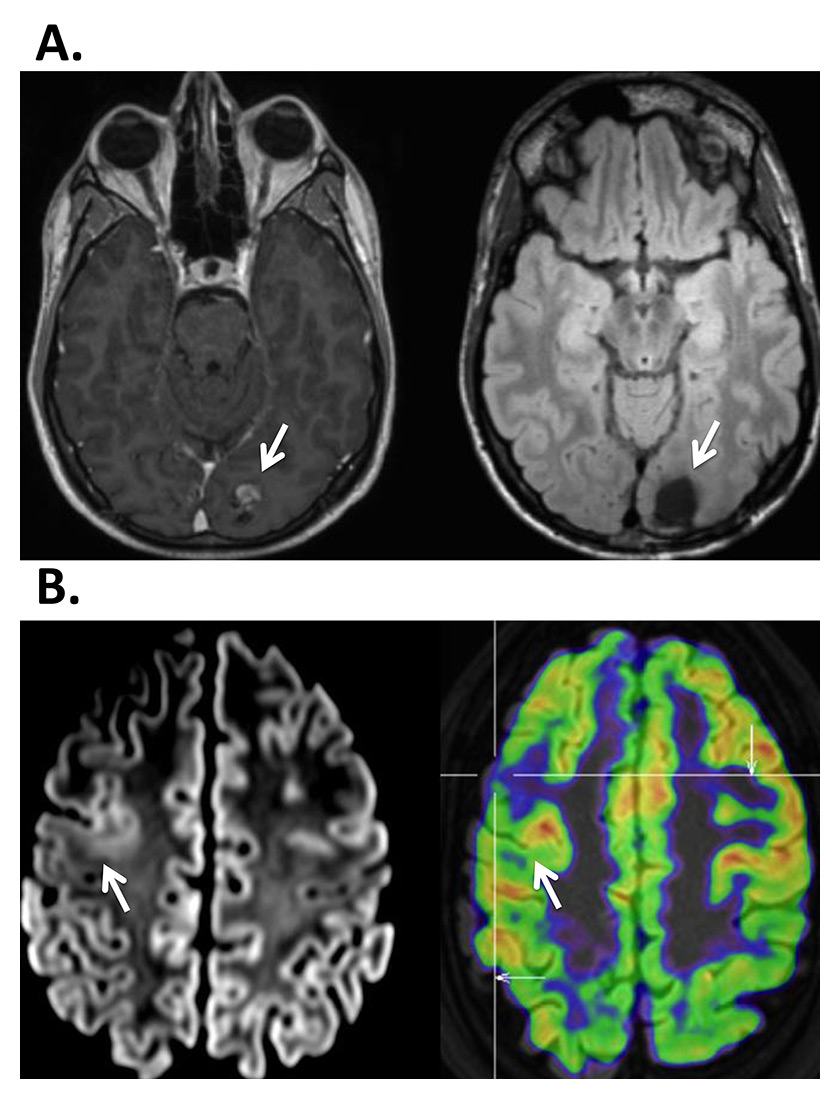

During the evaluation, two basic questions have to be answered: the location of the epileptic focus and identity of possibly adjacent vital cortex. The goal of epilepsy surgery is safe removal of the epileptogenic tissue without inflicting a (new) neurological deficit. Neurological, neuropsychological and psychiatric evaluations are basic elements of the preoperative work-up. The evaluation procedure includes the recording of several habitual seizures with long-term video-EEG monitoring in a specialised centre, with 24-h surveillance by specialised personnel, rapid access to intensive care and emergency CT. A high resolution MRI scan and, if possible, examination with other imaging tools (e.g. position-emission tomography [PET], single photon-emission-computer-tomography [SPECT], high-density EEG / electric source imaging [ESI]) are crucial in the identification of the seizure onset zone [96]. The more imaging examinations are concordant, the more likely there will be postoperative seizure freedom [97]. Figure 2 provides an example of multimodal imaging in a patient with bitemporal discharges.

Surgical results depend critically on the definition of the ictal and interictal EEG onset zone as well as on the presence of a lesion in 1.5-Tesla or, better, 3-Tesla high-resolution MRI, obtained with an epilepsy protocol, i.e. 1 mm slices for most sequences, as detailed elsewhere [98]. If the lesion is highly suspected or functionally localised with PET, SPECT or ESI, but not visualised in the high-resolution MRI, additional statistical analysis of the MRI may be useful and unravel the underlying epileptogenic lesion [99, 100] (fig. 3).

Figure 2

A 26-year-old patient undergoing multimodal imaging after a recording of bitemporal discharges with left predominance. A. MRI showed bilateral hippocampal atrophy with left predominance. B. left: PET showed a hypometabolism at the left mesioteporal lobe, right: Ictal-interictal substraction SPECT (SISCOM) showed an ictal hypermetabolism at the left mesiotemporal lobe. C: Combined EEG-fMRI showed a left hippocampal localization of spike-related BOLD changes. D. Electric source imaging (ESI) also showed a left localisation of spikes. With multimodal work-up left antero-mesial epilepsy was diagnosed.

EEG = electroencephalogram; fMRI = functional MRI; MRI = magnetic resonance imaging; PET = positron emission tomography; SPECT = single photon emission computed tomography. (The left side of the image is left.)